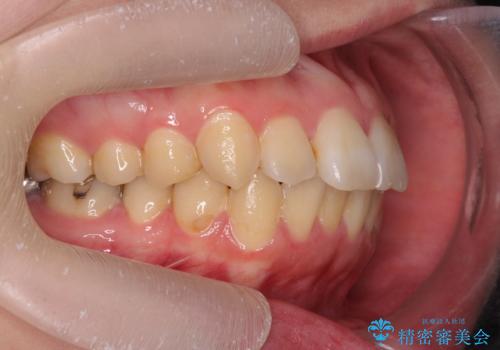

前歯の角度だけでなく内側に倒れ込んでいた奥歯もしっかり起こすことで咬合関係も理想的に仕上げています。